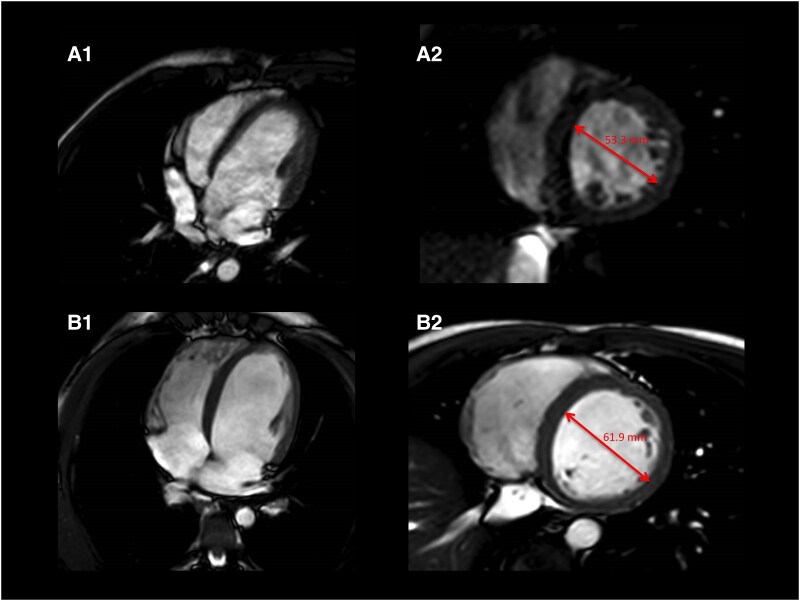

Case summary: A 17-year-old male with no pathological history was admitted to our institution due to wide QRS complex tachycardia with right bundle branch block morphology and left superior axis. The patient showed baseline infrahisian conduction abnormalities associated. Although left ventricular (LV) function and diameters were normal at admission, progressive LV dysfunction and dilation were observed during follow-up. Serial cardiac magnetic resonance imaging showed no evidence of myocardial scar. The electrophysiological study confirmed the diagnosis of clockwise BBRVT and a genetic study revealed a missense mutation in TNNI3K (p.Ile512Leu). Due to the high risk of AV block, no ablation was performed, and an implantable cardiac defibrillator was implanted. No recurrences were observed after 3 years of follow-up. Cosegregation analysis revealed cardiac conduction abnormalities and LV dysfunction in variant carriers.